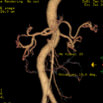

Liver Mass & Abd Aorta VR

占位性病变与腹主动脉及其主要分支血管的VR图像:显示占位性病变与其周围血管的相应关系